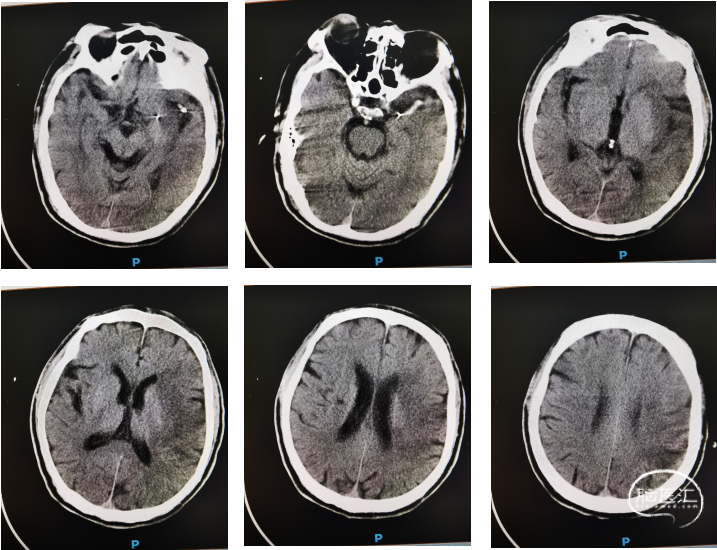

术中造影确认脑血流完全恢复,mTICI 3级,术后24小时复查头颅CT左顶叶少量渗出。

术后7天后患者NIHSS评分改善。CT提示渗出基本吸收,有部分缺血表现。

神志嗜睡,言语含糊,查体欠合作,双侧瞳孔等圆等大,直径约3.0mm,双瞳直接及间接光反射灵敏,右侧鼻唇沟变浅,伸舌居中,颈软,四肢腱反射正常,四肢肌力适中,左侧肢体肌力V级,右侧肢体肌力III级,双下肢病理反射阴性。出院前mRS 4分,NIHSS:8分。已转当地医院进一步康复治疗,仍在随访中。